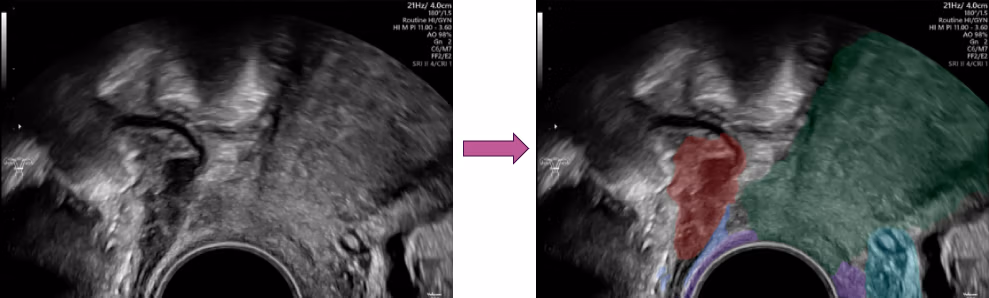

Hier setzt die KI an. Diese Bildanalysesoftware ist mit hunderten Bildern von gesunden und erkrankten Frauen trainiert und hat wahrscheinlich schon mehr Endometriosefälle gesehen als viele Gynäkolog*innen. Der Vorteil ist also, dass sie mit einem riesigen Erfahrungsschatz startet. Sie analyisiert das Videosignal, das vom Ultraschallgerät kommt, in Echzeit, und ist in der Lage, gewisse Organe und Strukturen zu erkennen. Auf einem zweiten Bildschirm wird so das ursprüngliche Ultraschallbild angezeigt, das nun aber zusätzlich halbtransparente, farbige Overlays enthält, welche das Bild «erklären» und zeigen, was gerade sichtbar ist. So werden zum Beispiel Gebärmutter, Blase, Eierstöcke, Gebärmutterbänder und eben auch Endometriosezysten farbig markiert, was sowohl der Untersucherin oder Untersucher, aber auch der Patientin helfen kann, die Anatomie besser zu verstehen. Ein besonderes Augenmerk liegt auf der tiefinfiltrierenden Endometriose, welche sofort rot markiert wird; zusätzlich macht die Software Screenshots von den Endometrioseherden, welche sich die Ärztin oder der Arzt im Review-Modus in Ruhe anschauen kann.

Links: Original-Ultraschall. Rechts: KI-Software markiert die Bereiche farblich: Endometriose (rot), Gebärmutter (grün), Vagina (violett), Bänder (blau).